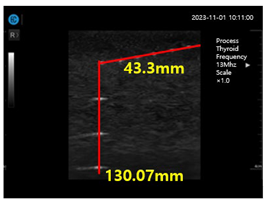

Figure 15a shows ultrasonic gel testing at various time intervals using the ATS-539 phantom. Figure 15b shows the sharpness of the image of the manufactured gelatin soft gel after storing it in alcohol and performing a sharpness test at 1 h intervals for 72 h. The results are presented in Figure 15b. In this paper, the experiment using a soft solid gel did not require IRB agreement. This research on the proposed gelatin soft solid gel showed its functionality to be better than that of ultrasonic gel, including on grayscale, echo, and color. This means that it can overcome the tissue density dead zone to increase high resolution performance. To help imaging accuracy, it is proven that gelatin soft gel, especially the soft solid gel, can replace ultrasonic gel to simplify disinfection and ensure permanent use. Image corrosion testing of gelatin soft solid gel for 30 min is shown in Figure 16a. Ultrasonic gels were tested at different times using an ATS-539 phantom, where the gel was soaked in ethanol for 72 h, as shown in Figure 16b. Afterwards, the gel’s condition was tested again. Finally, Figure 16c measures the imaging resolution of the gelatin soft tissue gel.

As shown in Figure 16, the individual values of the ultrasonic gel for grayscale, dead zone, vertical area, and horizontal area are 93.79 mm, 45.32 mm, 103.13 mm, and 83.86 mm, respectively. In contrast, the values for the soft solid gel are 105.64 mm in the grayscale, 34.48 mm in the dead zone, 141.0 mm in the vertical region, and 102.89 mm in the horizontal region. Therefore, the grayscale increased by 1.1 times, the dead zone remained the same, and the vertical zone increased by 1.2 times. As shown in Equation (12), the time value (T) in the horizontal zone was calculated by dividing that of the soft solid gel (x) by that of the American gel (y), resulting in a 1.2-fold increase. This calculation was performed by dividing the soft solid gel value by the corresponding ultrasonic gel value [25,26].